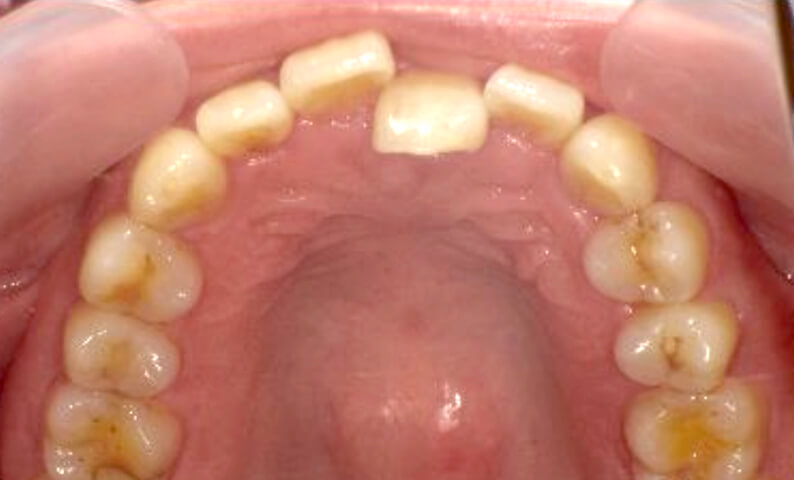

症例_002 上顎だけの部分矯正

治療期間:7ヶ月金額:30万円+税女性前歯のガタガタ上の前歯だけ

| Before | After |

|---|---|

|